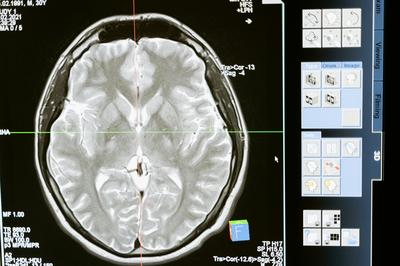

건강검진은 단순히 현재의 건강 상태를 확인하는 것을 넘어, 앞으로 발생할 수 있는 질병을 예방하고 건강한 삶을 유지하도록 돕는 중요한 역할을 합니다. 특히 한국인의 주요 사망 원인인 암, 심뇌혈관 질환 등은 조기에 발견하면 치료 성공률을 높일 수 있습니다.